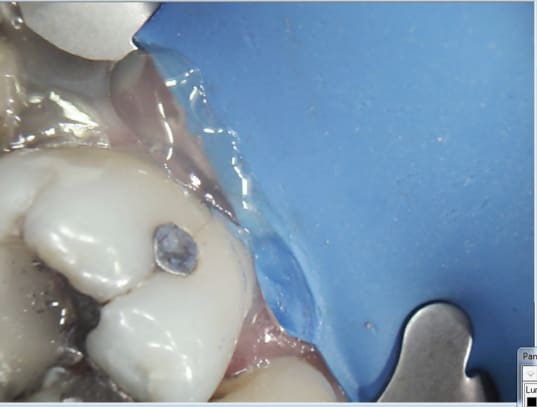

Le pb de la digue c'est les crampons qui tiennent pas quand le dent est fortement delabrée

> Le pb de la digue c'est les crampons qui tiennent pas quand le dent est

> fortement delabrée

Soit tu fais une reconstitution pré-endo, je crois que Chicot29 a une méthode rapide.

Soit tu prends des crampons pour dents délabrées et tu t'accroches sur la racine en gnaquant la gencive, après il faut étanchéifier si besoin, c'est ma méthode.

Ah ? reconstitution pré endo. Peak universal bond ( direct sans mordancage) luxacore Z, clip flow pour étanchéifier la digue le cas échéant.